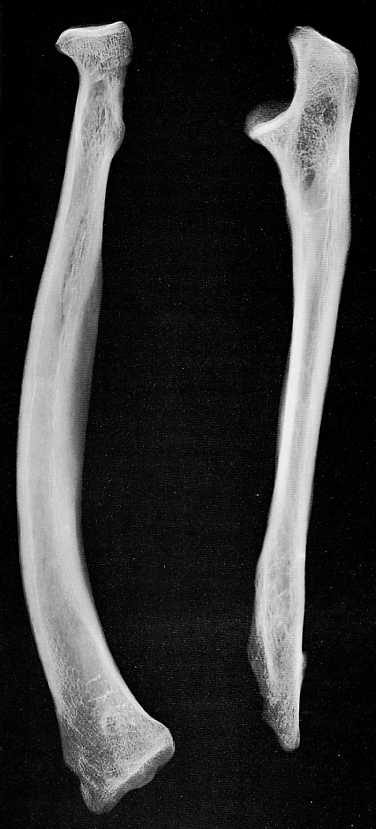

• Deux fémurs médiévaux présentent l’un, une fracture à la jonction des 1/3 moyen et inférieur, l’autre du col et du grand trochanter :

• le premier concerne un individu masculin de la nécropole de Néris - les - Bains, Allier [17 - 20] : la consolidation s’est effectuée en position vicieuse avec un énorme cal, qui a rejeté en arrière, le fragment inférieur avec raccourcissement de 5,5 cm et une forte angulation antéro - postérieure (cf.fig.2)..

• le second intéresse un individu féminin âgé, de la nécropole Saint - Just, de Lyon  [11 - 15]  il n’y a pas eu guérison et une pseudarthrose s’est développée postérieurement à l’incident traumatique (cf.fig.3).

Figure 2 : Fracture fémorale diaphysaire [Néris - les -Bains], vue de 3/4 antéro-médial.

Figure 3 : Fracture du col fémoral et du grand trochanter avec pseudarthrose ( nécropole de Saint-Just, Lyon)

Comme pour la traumatologie rachidienne, nous nous sommes livrés à une étude statistique des cas de fracture des os longs dont le résultat fonctionnel était connu :  le nombre total est de 215 fractures ( dont 132 pour les époques préhistoriques ).98,5 % des fractures préhistoriques sont consolidées (en regroupant les fractures quel que soit le développement du cal ) contre 94 % pour celles médiévales. La pseudarthrose est peu importante (1,5 et 6 % respectivement) avec cependant une augmentation importante pour le Moyen -Age : 4 fois plus!

Cette constatation nous a amenés à supposer que beaucoup de traumatisés médiévaux se confiaient a un rebouteux local à la compétence douteuse, parce que les vrais chirurgiens leurs étaient, géographiquement ou financièrement, inaccessibles [17]